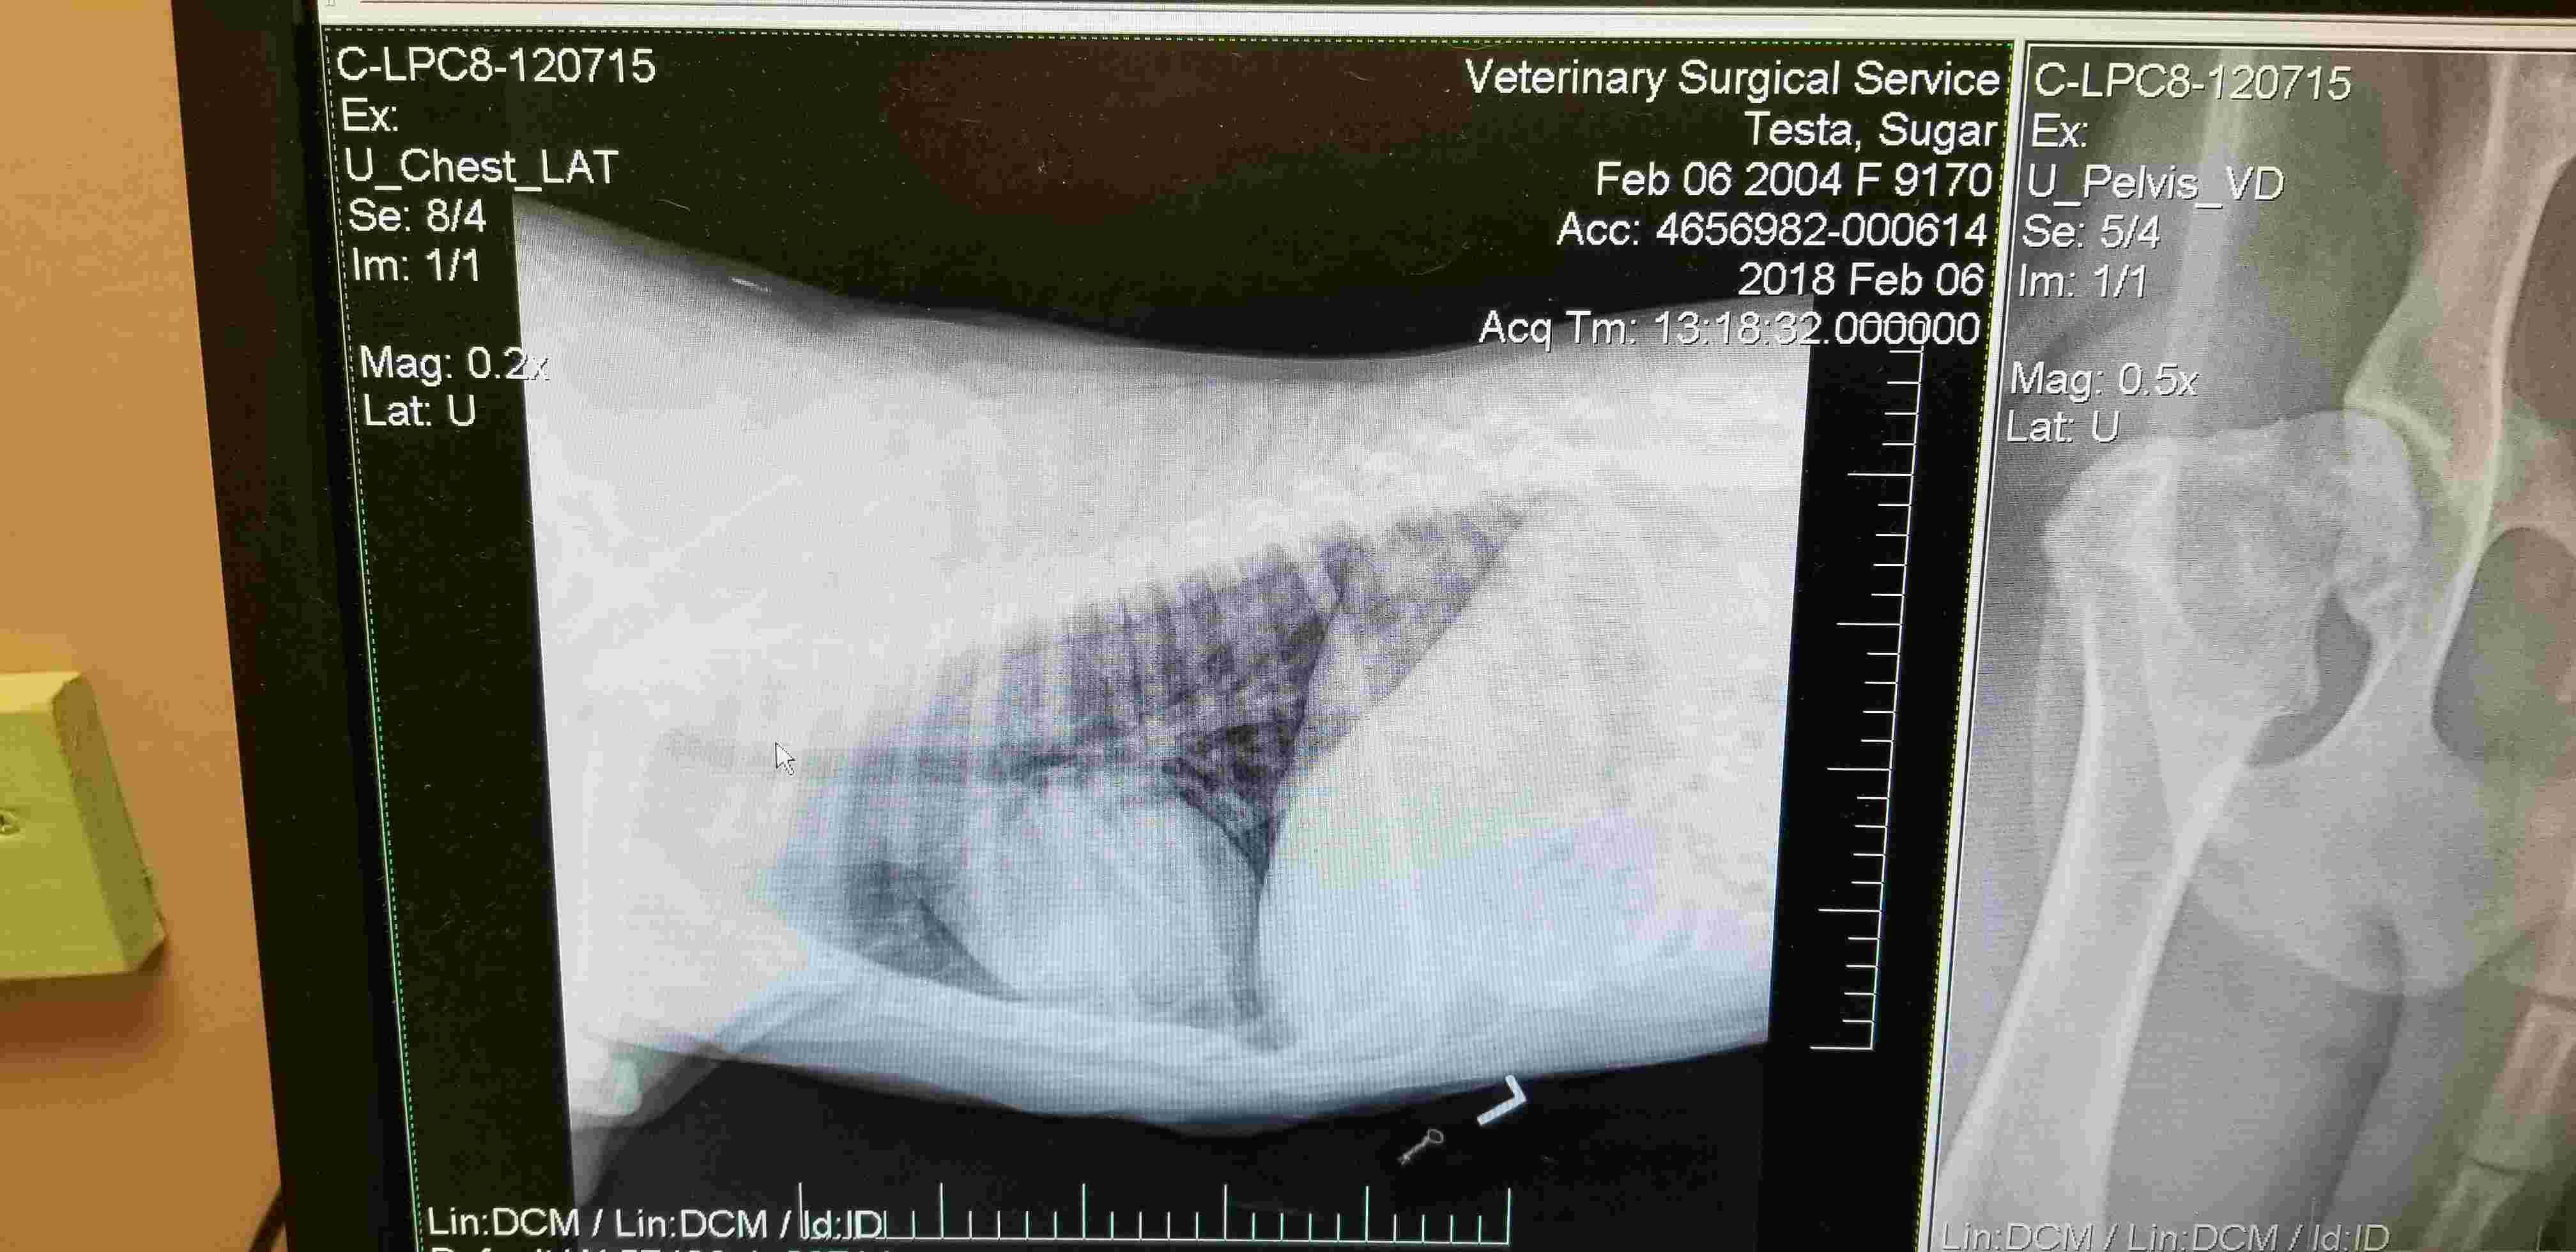

Pet's info: Dog | American Pit Bull Terrier | Female | spayed | 13 years and 8 months old | 45 lbs

Hello. Can you please review my Pitbull's x-rays and see if she has hip dysplasia and/or arthritis? Thanks Joe

Thank you for submitting your question regarding Sugar. She appears to have significant changes to both of her hips indicating severe arthritis. She also appears to have some mild arthritic changes in her left knee. Hip dysplasia is a congenital disorder where the hip joints do not develop properly leading to arthritis later in life. So this is the potential cause of the changes in her hips. I hope she is able to start pain medication to help with her mobility.